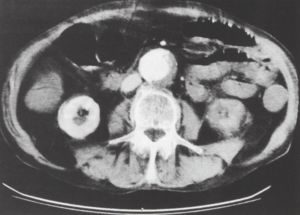

3. ábra.

Infrarenálisan kb. 7 cm átmérőjű aneurysma, az aorta meszes falú, jobb oldalon és dorsalisan sarló alakú hipodenz terület - fali thrombus. A retroperitoneumban magas denzitású képlet, haematoma.